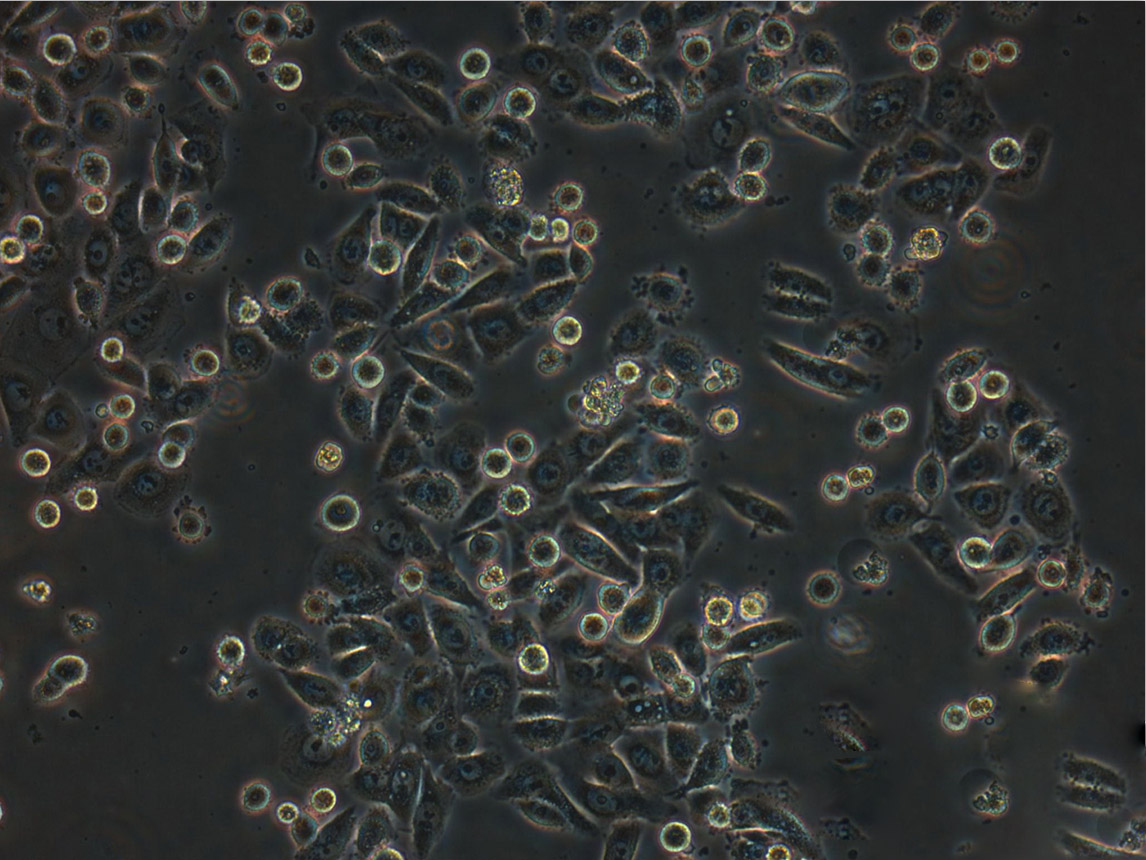

细胞生长:贴壁

细胞背景资料:小细胞肺癌;女性

细胞形态:上皮细胞样

细胞生长特性:贴壁